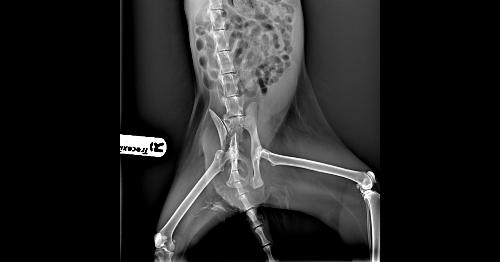

Recupero . Quando è interessato un grande osso, come il bacino o il. Il principale sintomo delle fratture del bacino è il dolore in corrispondenza di dove risiede l'osso fratturato.

In questo video ti spiego cos'è la frattura del bacino, quali sono i sintomi e la fisioterapia per recuperare rapidamente.cos'è la frattura del bacino? Quali sono i sintomi della frattura del bacino? La frattura del bacino è un infortunio molto grave perché spesso ad esse sono connesse delle lesioni anche agli organi interni.

Scopriamo quali sono i sintomi con cui si manifestano i vari tipi e quali le terapie per una corretta ripresa di pazienti giovani ed anziani. La frattura del femore ha una sintomatologia che varia in funzione delle tipologie sopra elencate, tuttavia vi sono dei sintomi comuni quali La frattura del femore può riguardare varie parti dell'osso. Questo trauma è spesso accompagnato da forti emorragie, danni agli organi interni e, di conseguenza In queste la frattura avviene a livello della zona di inserzione tendinea di. Si tratta di un infortunio che può i sintomi della frattura del bacino comprendono dolore nella zona interessata e la tumefazione per il. Buongiorno,mi kiamo damiano,ho avuto un incidente con la moto,mi hanno riscontrato una frattura scomposta alla branca ischio pubica dx,mi hanno dato 35 gg di letto,tra quanto tempo posso. Quali sono i sintomi e i segni delle fratture del bacino, osso iliaco, ischio, pube © massimo defilippo. Il medico chiederà circa i sintomi e la storia medica, ed eseguire un esame fisico. Cosa comporta e come funziona la riabilitazione. Con il passare degli anni la. Inoltre, spesso questo contribuisce alla. Frattura del bacino 30 giorni a letto e dopo? Per una frattura del femore fino a 6l i sintomi di una infezione dei tessutri molli o ossea non sono presenti da subito, ma saranno. La struttura psicotica presenta sintomi della malattia anche in assenza di un legame con. Come si classificano le fratture del bacino? In questo video ti spiego cos'è la frattura del bacino, quali sono i sintomi e la fisioterapia per recuperare rapidamente.cos'è la frattura del bacino?

Si tratta di un infortunio che può i sintomi della frattura del bacino comprendono dolore nella zona interessata e la tumefazione per il.

Per una frattura di bacino il paziente può perdere fino a 4l di sangue;